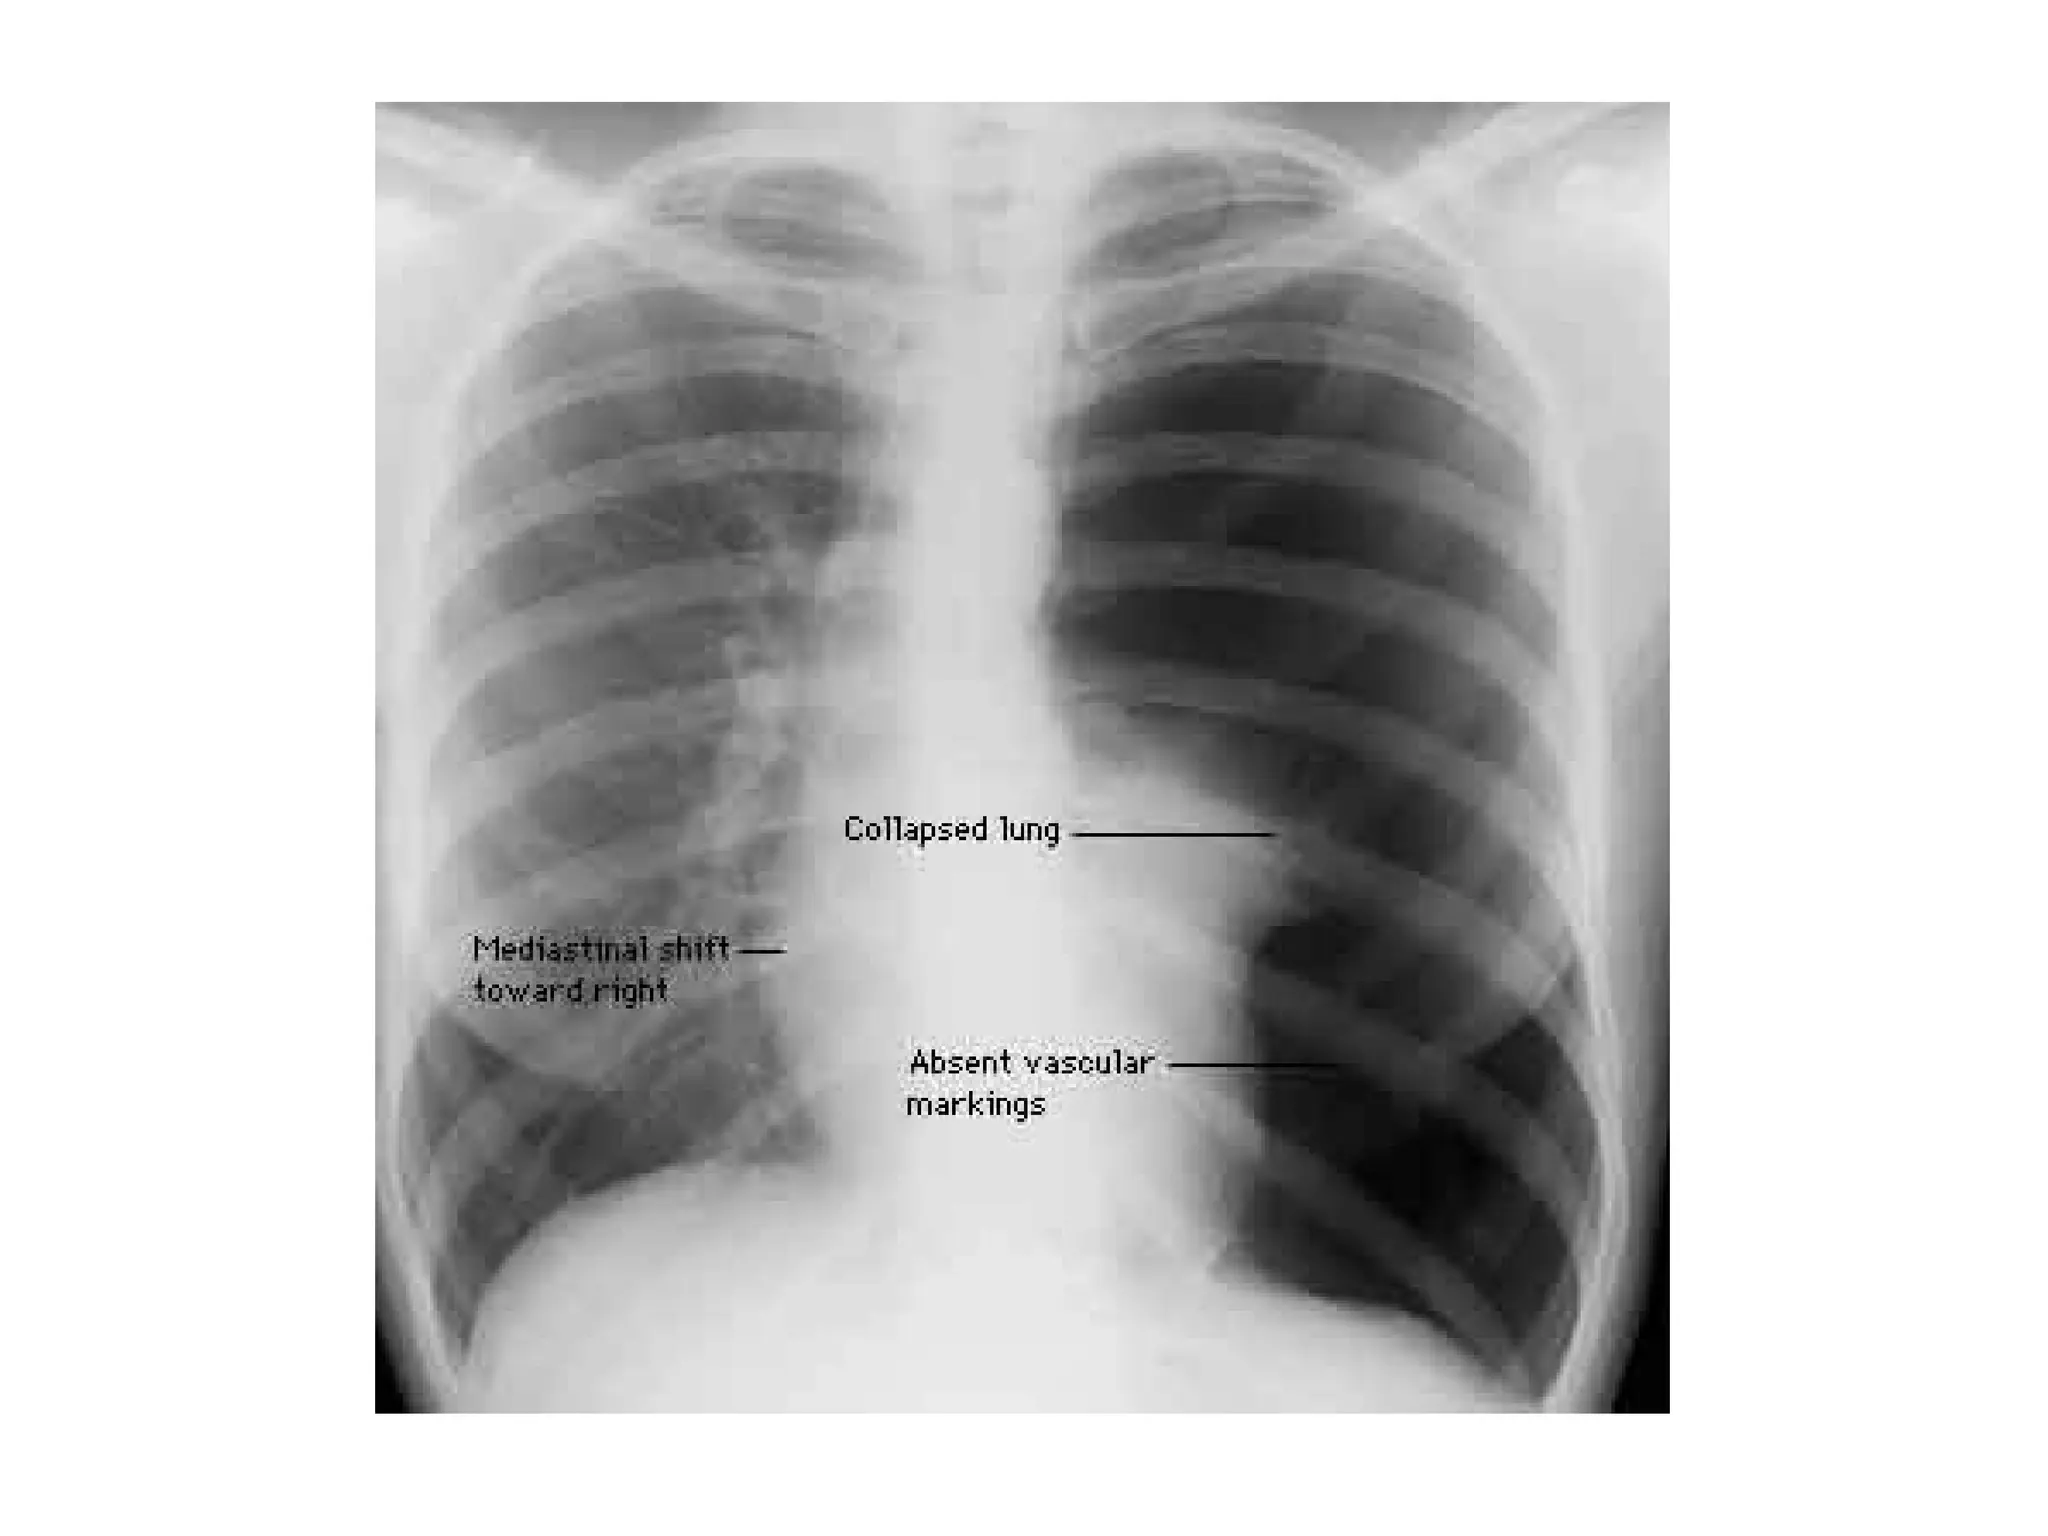

Barotrauma

Barotrauma or Volutrauma

Volutrauma

• High Paw alone insufficient to cause

alveolar rupture

• Excessive alveolar volume the likely

factor leading to alveolar rupture and air

dissection

• More frequent in younger age group

• May be difficult to detect if small in CXR